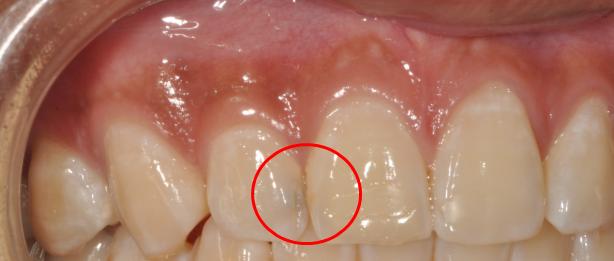

经常使用牙线的人可能会早期发现邻面龋。使用牙线时,来回拉动,可发现牙线撕裂伴有毛刺。这是邻面龋的早期表现。

随着邻面龋的进一步发展,肉眼观察牙齿邻面颜色暗黑,对光线的透射性减弱。X线显示牙齿邻面出现三角形低密度阴影。牙齿遇冷热酸甜等刺激产生酸痛,经常出现大量食物残渣嵌塞,伴有腐臭味。龋损进一步扩展时,会发生颌面牙体组织的折裂。